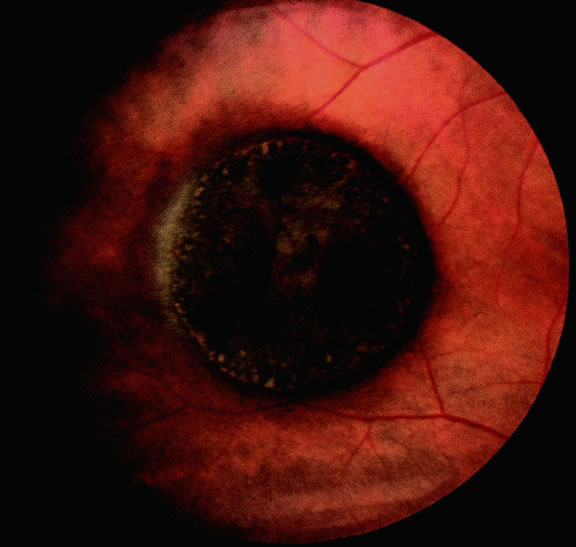

Many choroidal melanomas have a characteristic mushroom or collar button configuration that results when the tumor breaks through Bruch's membrane (Figs. 19, 20, 21, and 22). In such cases there is often secondary choroidal, subretinal, or vitreous hemorrhage. Dilated, intrinsic vessels often are evident in the mushrooming dome of nonpigmented melanomas. The vessels are obscured in more pigmented tumors.48

Fig. 19. Fundus photo of mushroom-shaped choroidal melanoma with nonpigmented dome. Configuration indicates that tumor has ruptured through Bruch's membrane.

Fig. 20. Gross photo of mushroom-shaped choroidal melanoma. Amelanotic dome of melanoma anterior to break in Bruch's membrane elevates and detaches retina. Mushrooming head of tumor has a rough papillary surface and contains many vessels.

Gross Pathology

Choroidal melanomas initially arise in the stroma of the choroid. In early cases, the profile of the sectioned tumor is oval or almond-shaped, and its tissue usually appears relatively cohesive after fixation (Fig. 24). Although some tumors diffusely infiltrate the uvea, most uveal melanomas are relatively well-circumscribed tumors with distinct margins. In many cases the growing melanoma perforates Bruch's membrane and enters the subretinal space where its apex typically assumes a spherical shape that often is likened to a mushroom or collar button (see Figs. 19 to 22.). Dilated vessels often are found in the mushrooming head of the tumor because the ends of Bruch's membrane exert a compressive cinch-like effect on the waist of the tumor (see Fig. 22). Rupture of Bruch's membrane was present in 87.7% of 1527 large- or medium-sized melanomas examined in the COMS.84 Retinal invasion was present in nearly half (49.1%), and tumor cells were found in the vitreous body in one fourth.